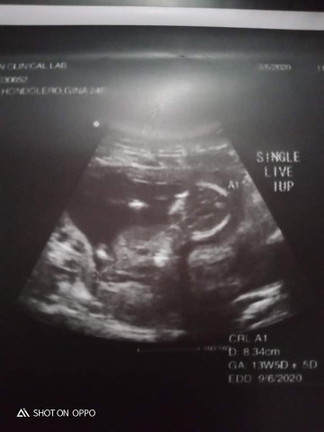

Eto na baby ko 13 weeks 5 days preggy ... swerte ko sknya kase akala ko nuon ectopic sya buti nlng ndi ... thank you lord and pa ultrsound na din ko to make sure na maayos ung kalagayan nya at may heart beat .